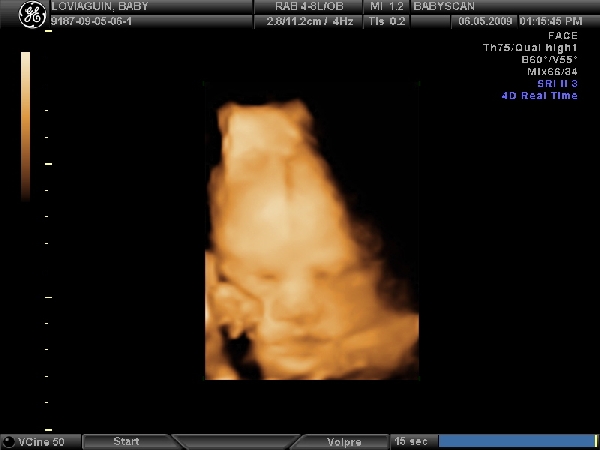

Nemsokara keszulok 3d-re!!!!Delutan 1/2 2-re kell menni,remelem most ezek jobban odafigyelnek majd,mert az elozo,ahol a 21.heten voltunk,na az katasztrofa volt....unott csaj,folyamatos basztatas hogy meg kicsi,ennek igy semmi ertelme... :shock: :evil:

Ezeknel mar voltam a 12.hetin,es a genetikai uh-n,es rendesek,turelmesek,kedvesek voltak.

Na es akkor...!

Megvolt az uh,edes kis lanykat novesztgetek pocakomban.Kisse szegyenlosnek mutatkozott,az istenert sem akarta a kezet elvenni az arca elol,sot kesobb a masik kezevel is fogta a fejet...es egy lab is bejatszott a kepbe :lol: :lol: :lol:

Kaptunk vagy 40db.kepet 8) lattuk minden porcikajat!Vegre a ket szemunkel a nuncijat is :lol: !Turelmes,rendes,kedves dokineni csinalta....elegedett vagyok apaval egyutt.Sikerult megint elpityerednem,persze a buszke apuka is csak amuldozott a lanyan!!!

Mereteink:

BDP(fejatmero):7,56cm

HC(fejkorfogat):28,0cm

AC(haskorfog.):26,78cm

FL(combcsont):5,96cm

HL(felkarcsont):5,49cm

becsult suly:1654gr.

Szoval teljesen rendben vagyunk,remenykedtem hogy nem produkalunk orias mereteket,mindenki riogat a hasmeretem alapjan....jo lenne ha nem lenne egy benga orias bebi :lol: :lol: 8)

Meretek alapjan julius 8 koruli a szuletesi ido.De nem modositok,jo ez igy ez a tol-ig idopont...